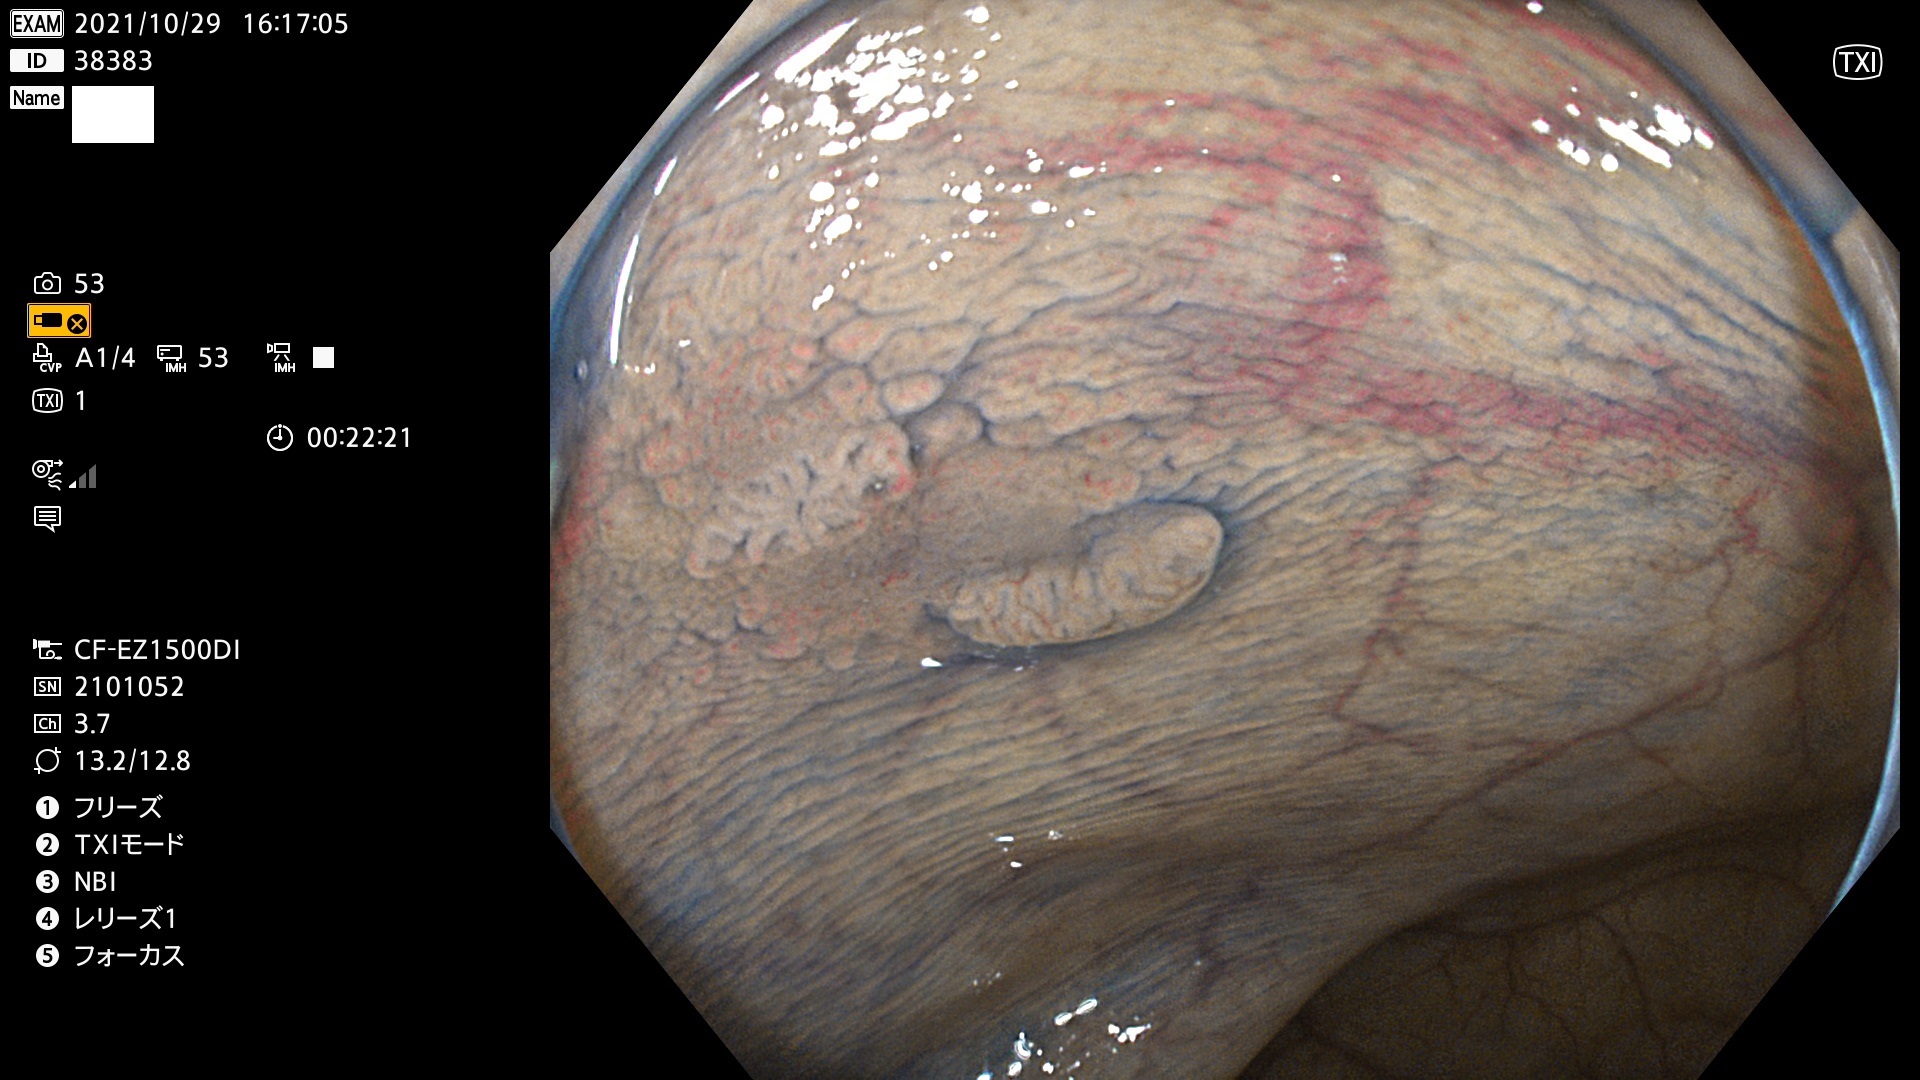

38300 38301 38302 38303 38304 38306 38307 38308 38309 38310 38311 38312 38313 38314 38315 38316 38317 38319 38321 38322 38323 38324 38325 38327 38331 38332 38333 38334 38337 38338 38339 38340 38341 38343 38346 38348 38349 38350 38351 38352 38353 38354 38355 38358 38359 38360 38361 38362 38363 38365 38366(SSAP) 38368 38369 38370 38371(SSAP) 38372 38374 38375 38376 38377 38378 38380 38381 38382 38383 38384 38385 38386 38388 38389 38391(SSAP) 38395 38397 38399

発見困難で危険性の高い平坦型病変(上記100名より抽出)